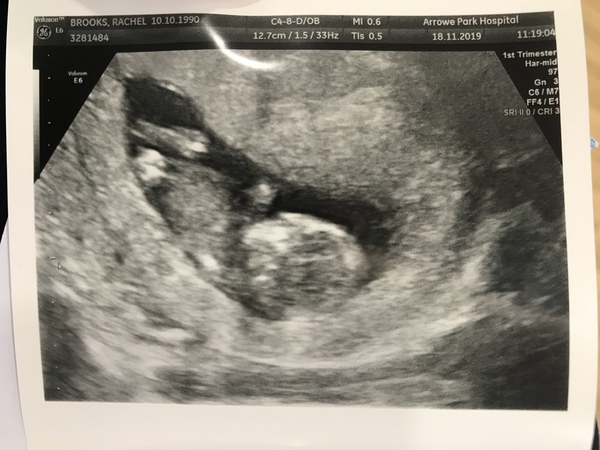

RacBell · 18/11/2019 14:01

Hi all, just had my 12 week scan. Baby wasn’t behaving today and wouldn’t budge from curled up position and doing a head stand but otherwise all looks perfect. Given due date 29/5. Has anyone else been given this date? I’ve got a sneaky feelings it’s a girl but don’t want to convince myself too much 😩 I already have 2 boys ☺️